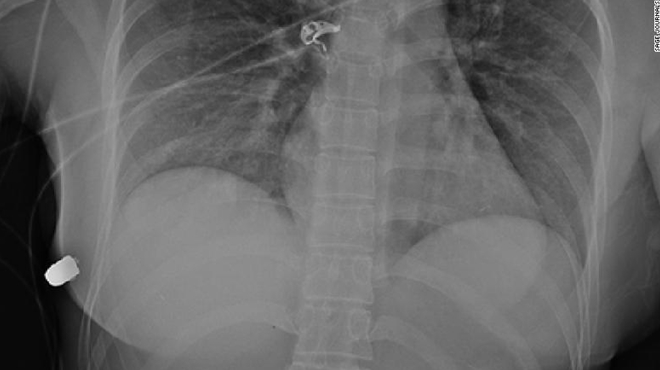

Ảnh chụp X quang, nguồn CNN.

Qua hình chụp X quang chấn thương, các bác sĩ có thể phát hiện ra viên đạn ở thành ngực bên phải, một xương sườn bị gãy, bong bóng khí ở vú trái, và kết luận rằng viên đạn đi từ ngực trái sang thành ngực phải.